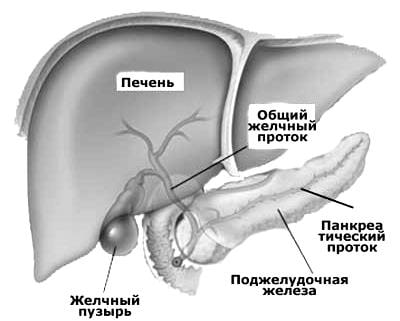

ВИЗУАЛИЗАЦИЯ ЖЁЛЧНЫХ ПРОТОКОВ

Изобретение относится к эндоскопии и рентгенологии. Оно может быть использовано для диагностики и лечения заболеваний, связанных с поражением «жёлчных протоков» у пациентов с «холедоходуоденостомией» (ХДС).

Как поясняют авторы, в хирургии (при наличии «механической желтухи») широкое распространение получили такие оперативные вмешательства, как различные варианты ХДС. Пациенты (после проведения подобных операций) могут нуждаться (с целью уточнения причины «механической желтухи» или её рецидива в послеоперационном периоде) в проведении прямого контрастирования «жёлчных протоков».